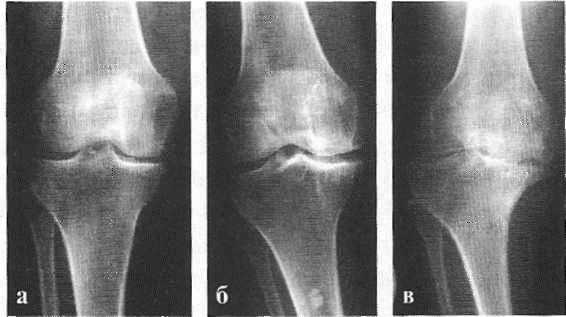

Рентгенологическое исследование помогает поставить диагноз, но не дает прогнозов по дальнейшему развитию симптомов заболевания. Рентгенограммы могут показать обширные изменения, но это не всегда означает в клинике сильную боль или нетрудоспособность пациента.

По данным исследователей, у 76% пожилых людей, предъявляющих жалобы на боль в коленях, на рентгенограммах обнаруживается гонартроз. [2] [7] [17] По статистике, чаще заболеванием страдают женщины, что связано с гормональной перестройкой после 45 лет. [12] [19]

В подавляющем большинстве случаев достаточно осмотра и рентгенограммы коленного сустава в двух проекциях (прямой и боковой). [2] [19] Клинические данные и снимки позволяют определить стадию заболевания.

На ранних стадиях заболевания, при незначительных изменениях в костной ткани, рентгенологическое обследование не настолько ценно. [5] [8] На этом этапе гонартроз возможно диагностировать благодаря артроскопии. [5] [8] Точность метода очень высока, останавливать может только его инвазивный характер и цена.